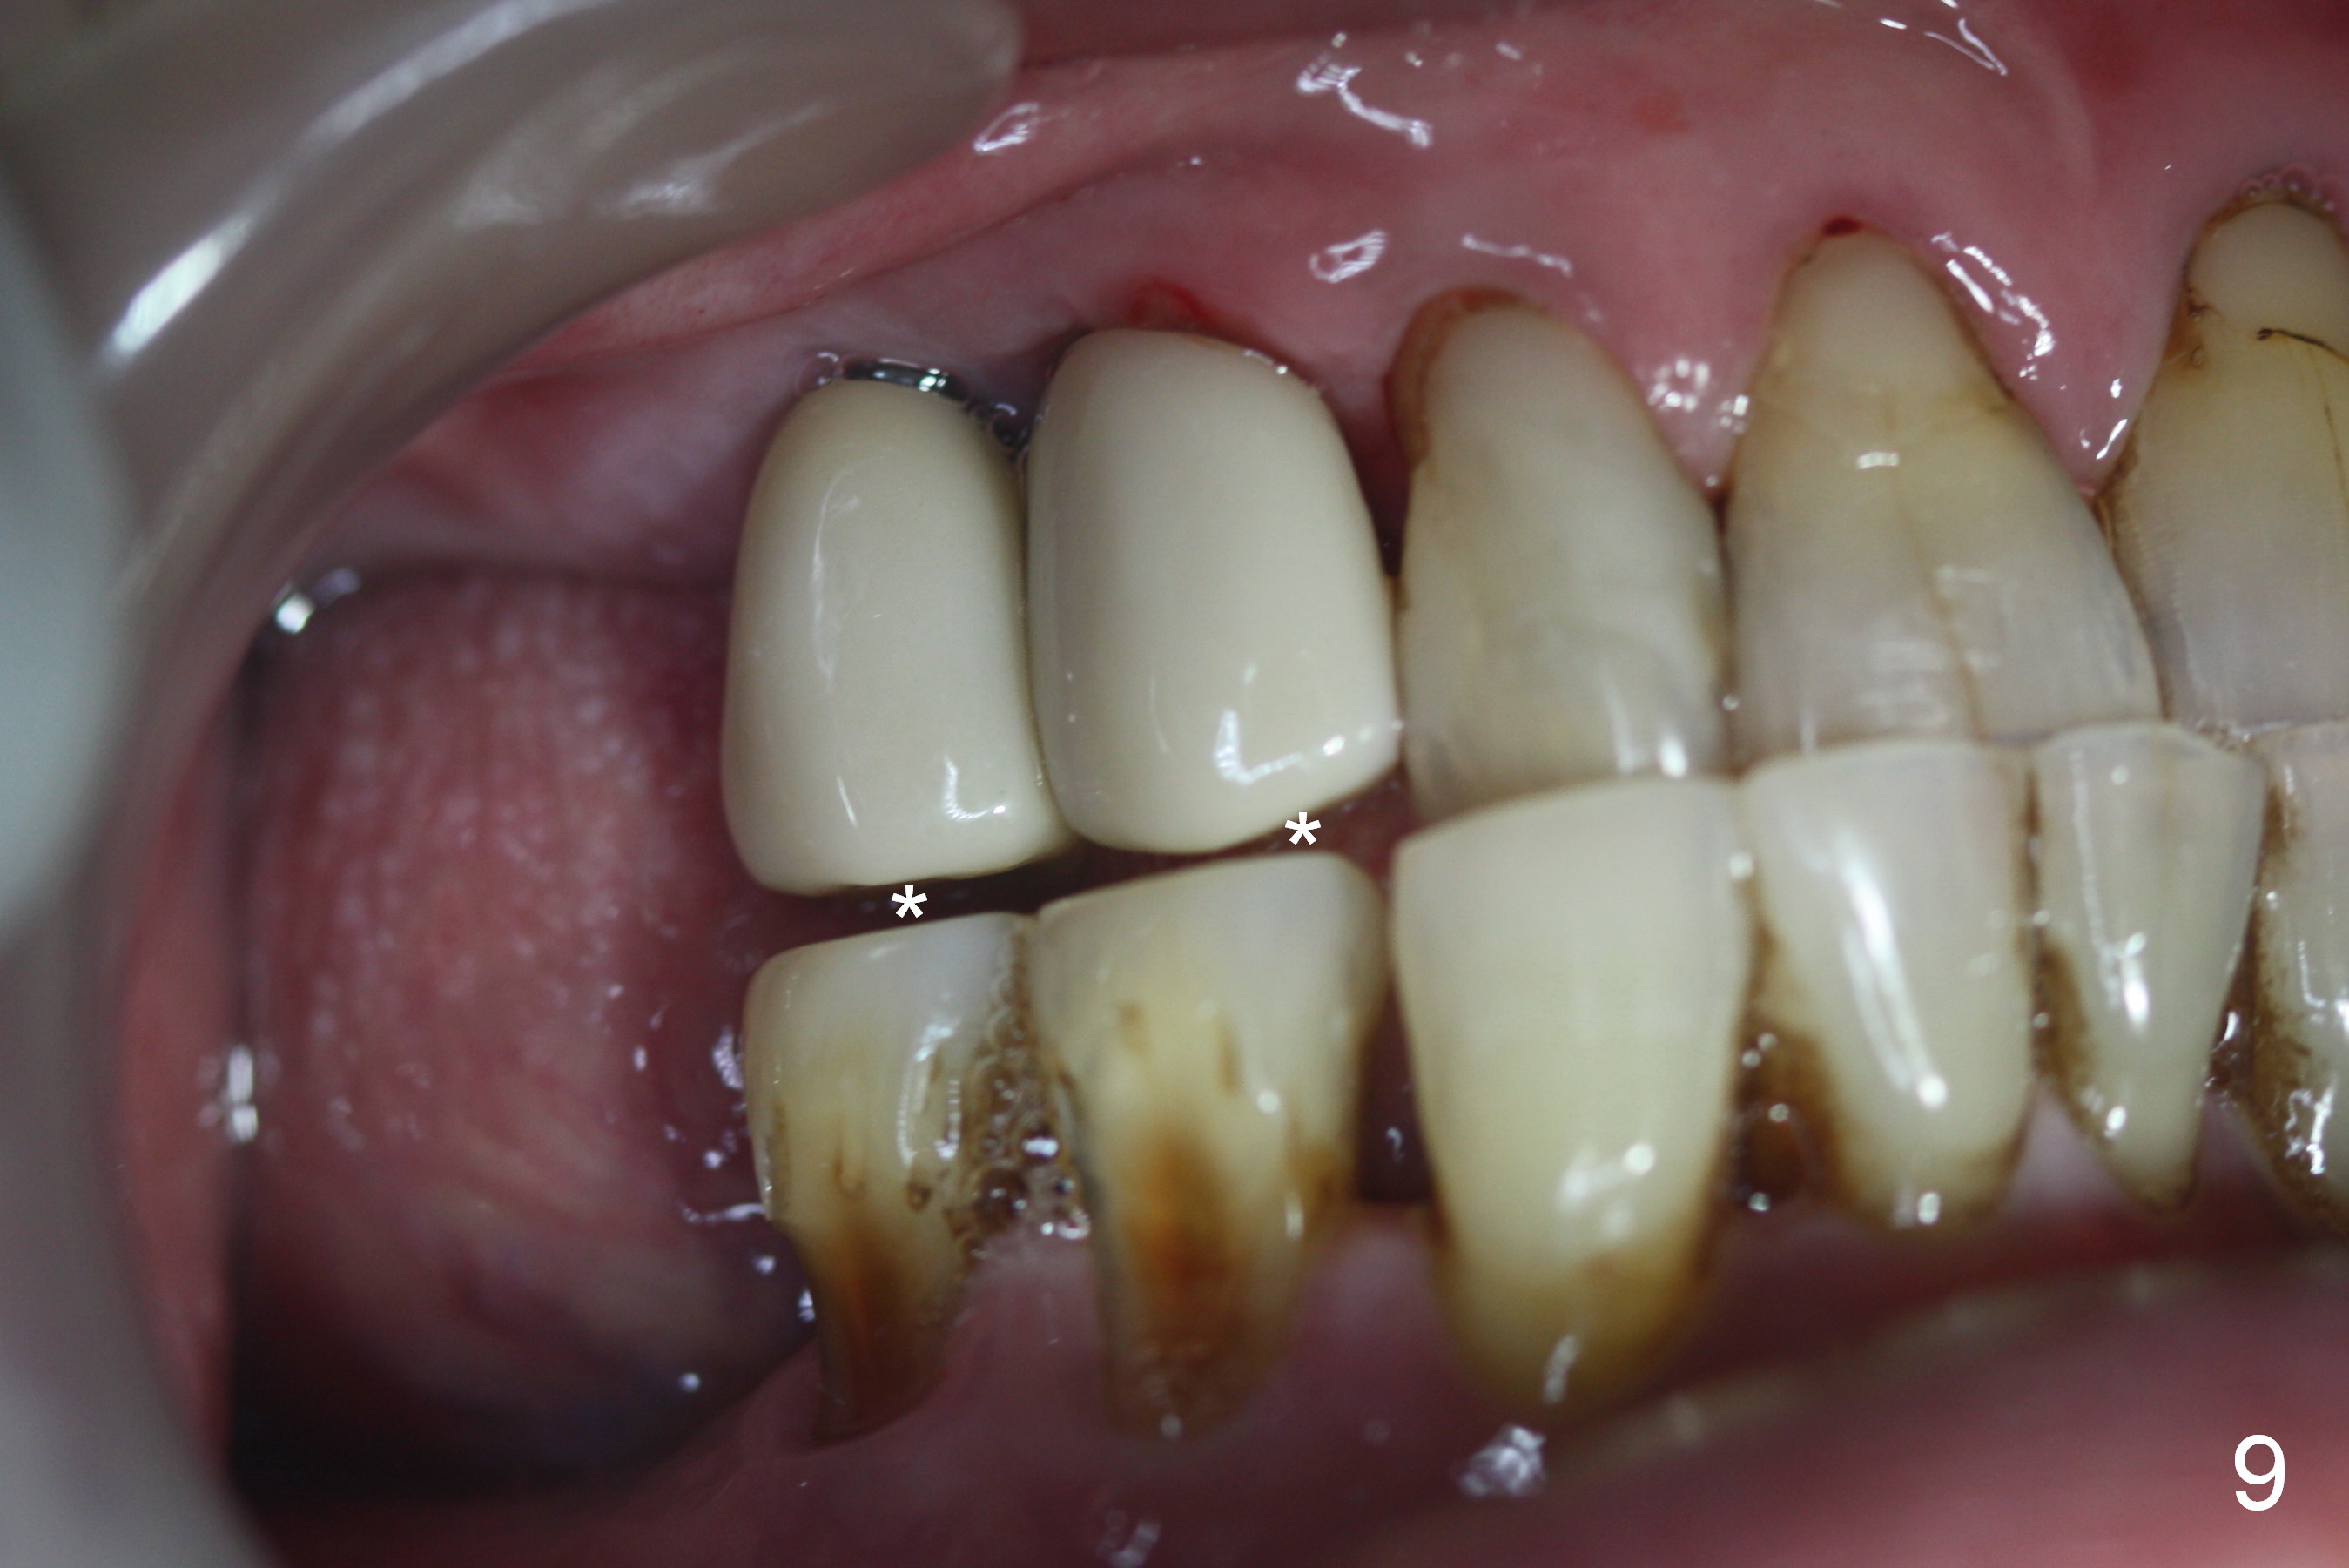

Several of CK's upper teeth (apparently in cross bite) are to be restored with implants (Fig.1). The first two are #5 and 6; note the oval roots (Fig.2). After extraction, and curettage, osteotomy starts in the palatal aspect of each socket. The 1st intraop PA shows that the trajectory at #6 is incorrect (Fig.3). After adjustment, osteotomies look parallel (Fig.4: D: 3.5x20 mm drill; T: 4.5x20 mm tap). This suggests how important it is to use parallel pins to check initial osteotomies for neighboring implants (Fig.3). The trajectory of the implants remains acceptable (Fig.5: 4.5x20 mm with insertion torque »60 Ncm); so is the position of the implants (as palatal as possible; Fig.6 (*: bone graft)). Immediate provisionals are fabricated in cross bite.

Bone density in the distal gap of #5 appears to have increased 3 months postop (Fig.7). Prior to definitive restoration cementation (3.5 months postop), the buccal plate does not collapse (Fig.8). There is no occlusal contact of the new restorations (Fig.9 *), probably due to bite discrepancy (Fig.10,11).